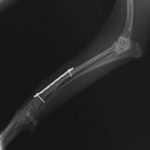

症例:交通事故による椎体脱臼

柴犬:9歳、避妊雌

交通事故直後、胸腰部に激しい疼痛、両後肢に完全麻痺を認め、シェフシェリントン徴候を呈していました。レントゲン検査において、第11-12胸椎間の脱臼が認められました。

脊髄の減圧、脊柱管の再構築・安定化を目的に、片側椎弓切除術およびMatrixMANDIBLE Plateによる椎体固定を実施しました。

隣接椎体を架橋するようにプレートを設置しました。

術後レントゲン写真